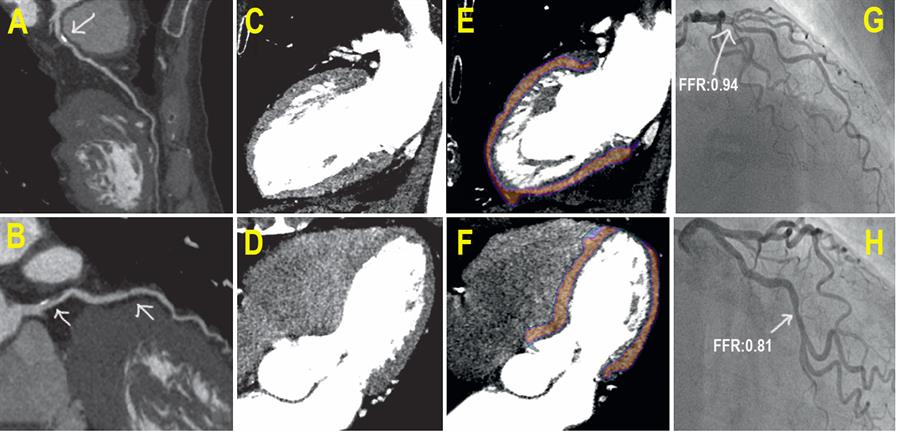

A 76 year old patient symptomatic, with mixed and calcified obstructive plaques

(A) Rest coronary CTA shows calcified obstructive plaques of the proximal left anterior descending coronary artery. - (B) Rest coronary CTA shows mixed obstructive plaque of the proximal and mid left circumflex coronary artery. - (C to F) Stress CTP during adenosine infusion shows normal myocardial perfusion as indicated by the homogeneous gray color (C and D) and orange color code (E and F) in 2-chamber and 4-chamber views of the left ventricle. - (G) ICA shows mild left anterior descending coronary artery stenosis with normal FFR (0.94). - (H) ICA confirms left circumflex coronary artery stenosis (50%) but with normal FFR (0.81).